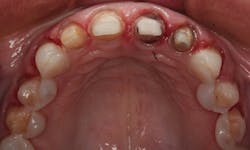

The old crowns were removed; the preparations for the maxillary lateral and central incisors were refined. Veneer preparations were completed for the canines and premolars. In Figure 5, you can see the preparations for four all-ceramic crowns and six veneers. Note that even though there were slight rotations, it was not necessary to break the contacts between the bicuspids and cuspids. This allowed for a more conservative approach that was less invasive. The prepared teeth are shown from the facial view in Figure 6. A new occlusal registration was made using Futar.

Figure 6: Facial view of the prepared teeth